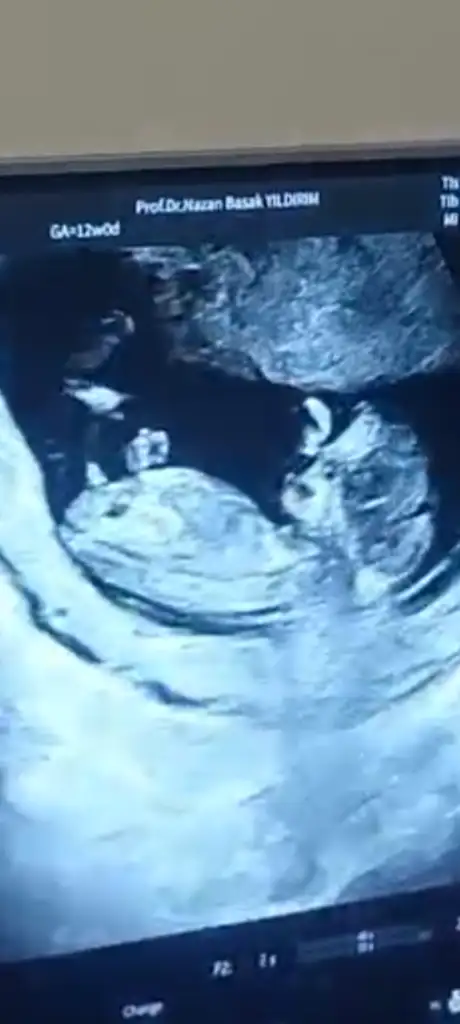

12+0 da doktor kontrolünde ilk kız bebek dedi sonra erkek dedi sonra emin olamadım 16 haftada kesinleetireyim dedi anlayan varsa yorum yapabilir mi

Eklentiler

• Screenshot_2025-12-17-10-02-29-331_com.miui.gallery.webp

Screenshot_2025-12-17-10-02-29-331_com.miui.gallery.webp

22,7 KB · Görüntüleme: 5